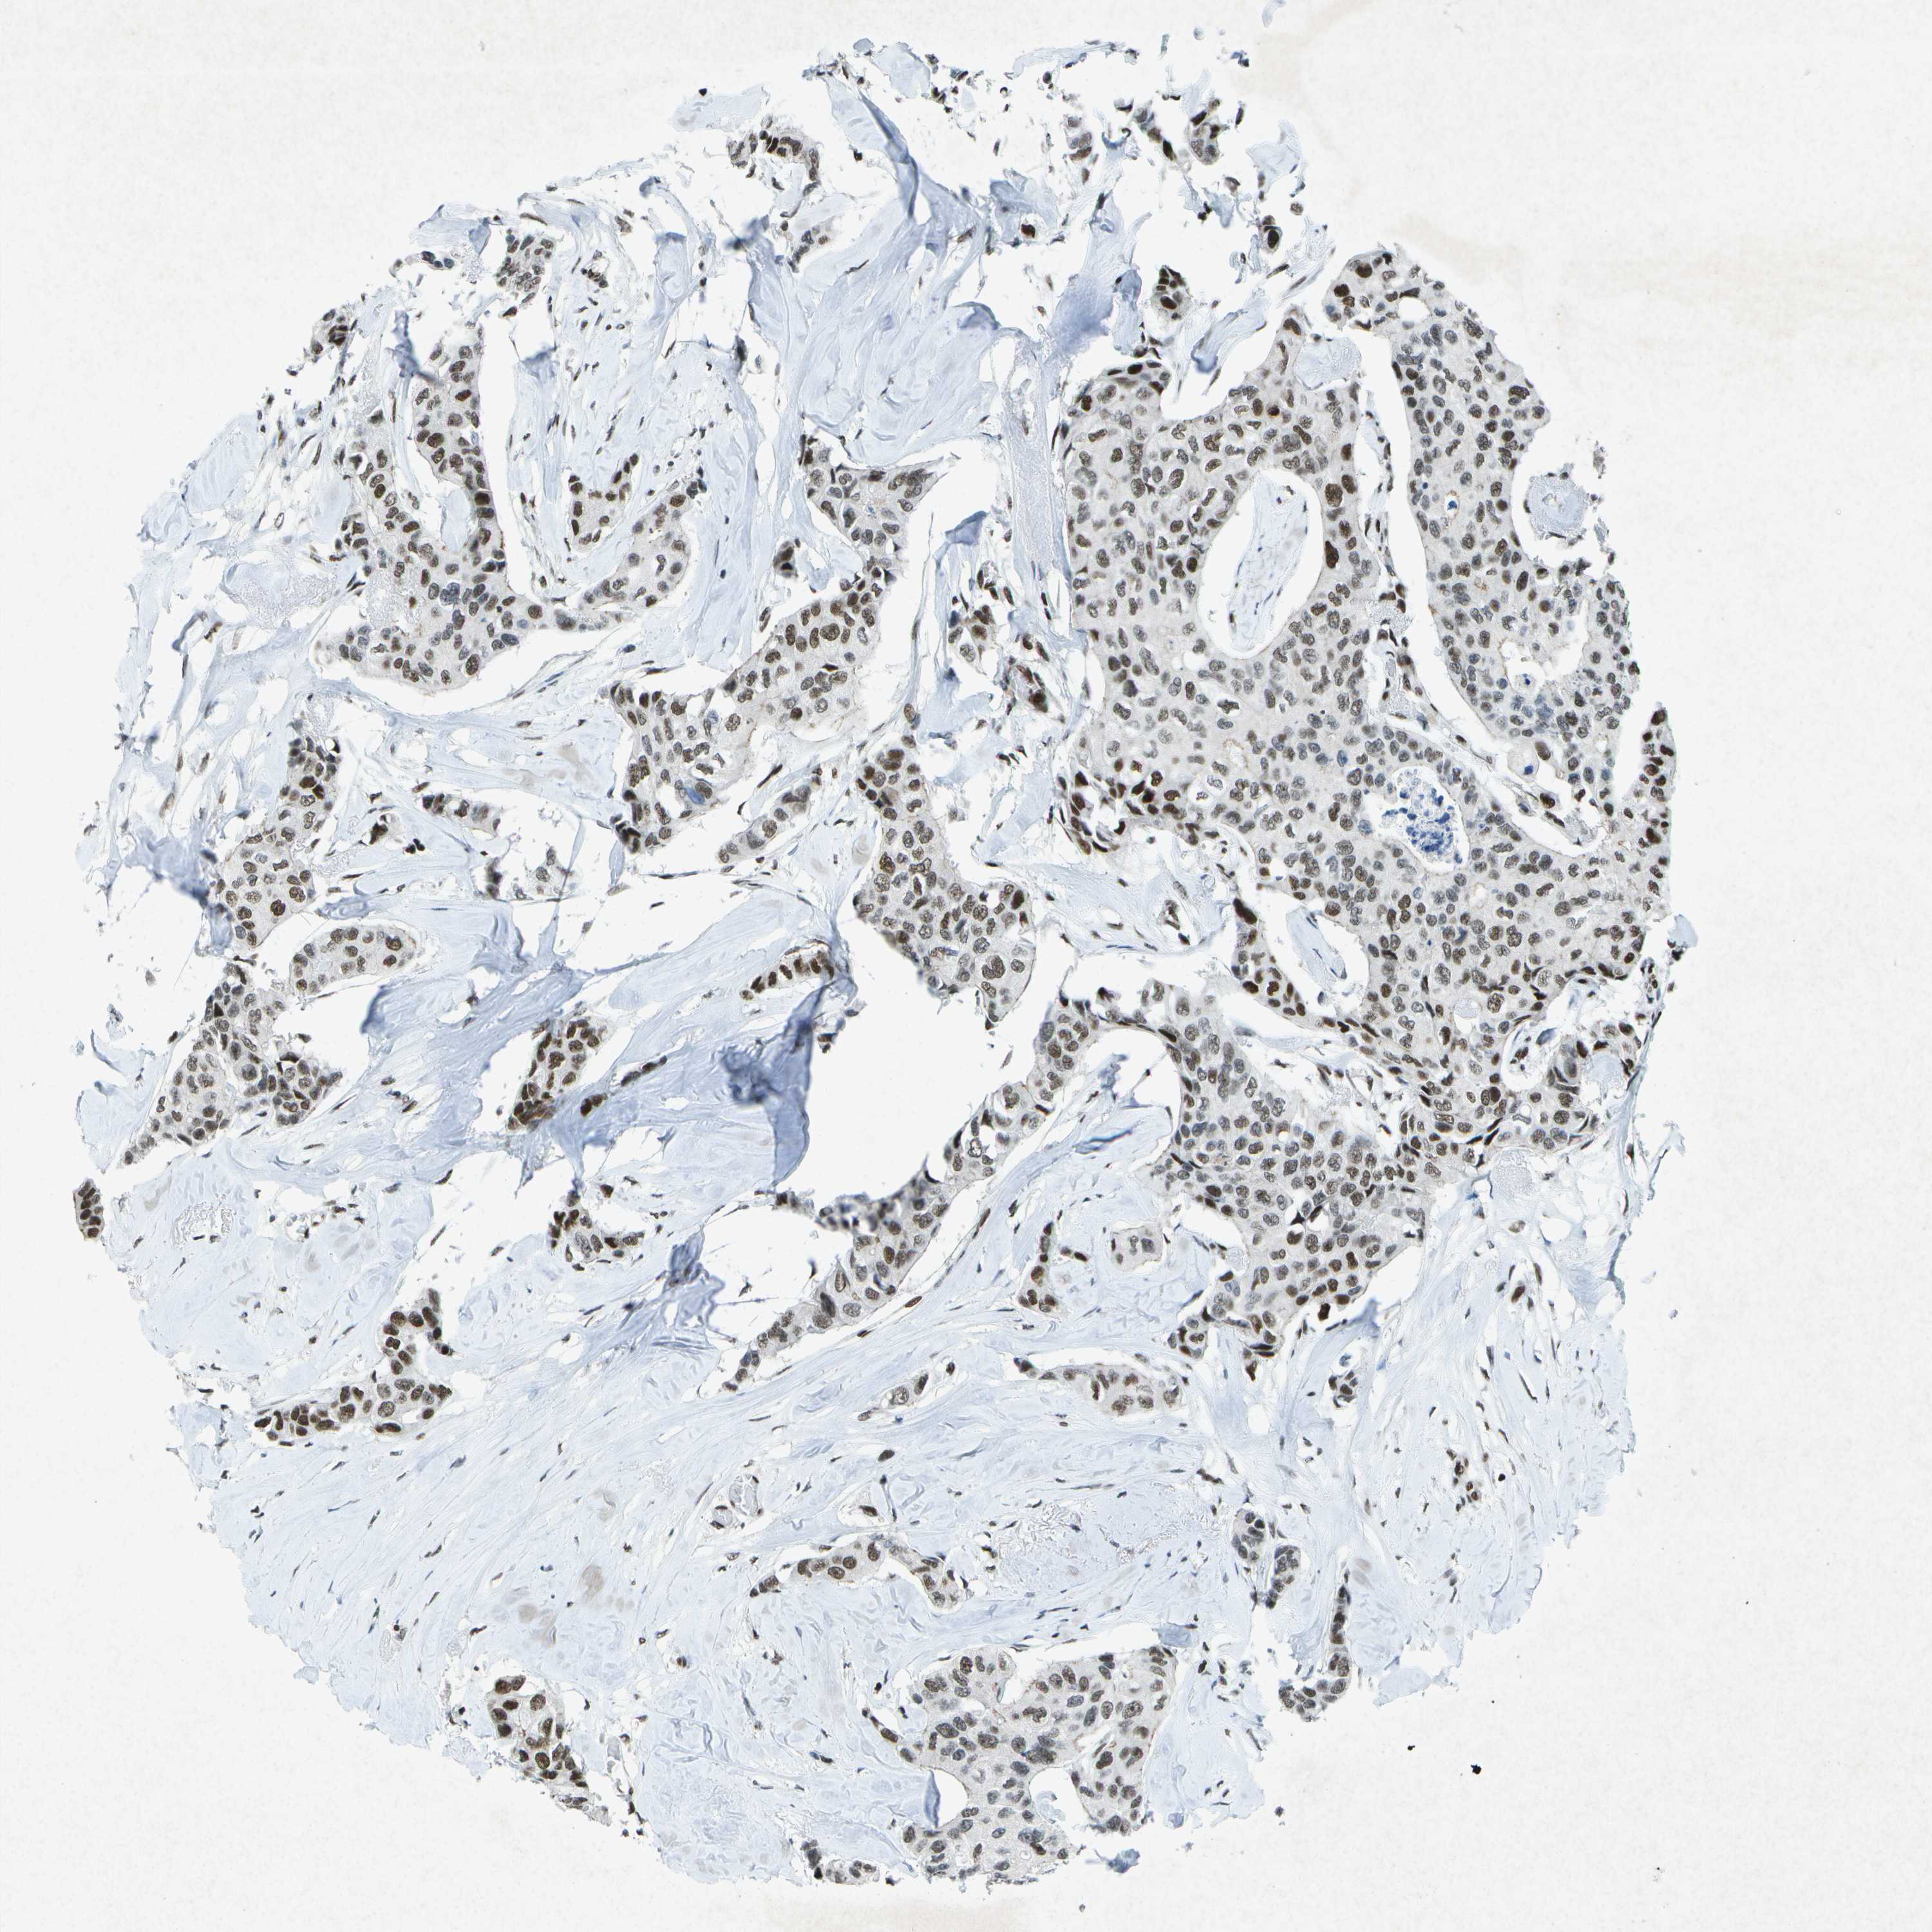

BRCA TCGA BRCA VALIDATION PROTEIN EXPRESSION

Breast cancer

Human cancer